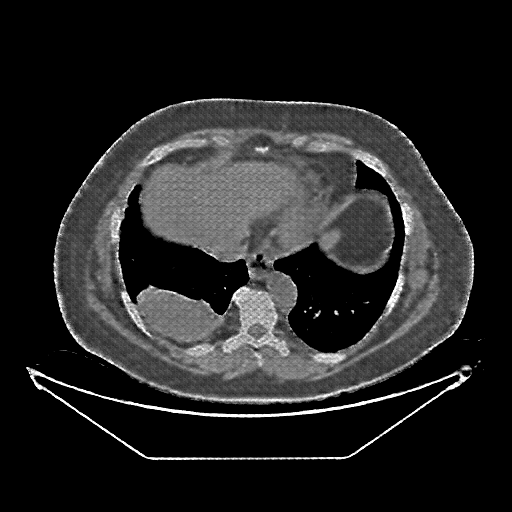

Generated VENOUS CT scan (A→B translation)

No window - Raw intensity values

Lung window (WL -600, WW 1500 β†’ Low βˆ’1350, High +150)

Mediastinum window (WL 40, WW 400 β†’ Low βˆ’160, High +240)